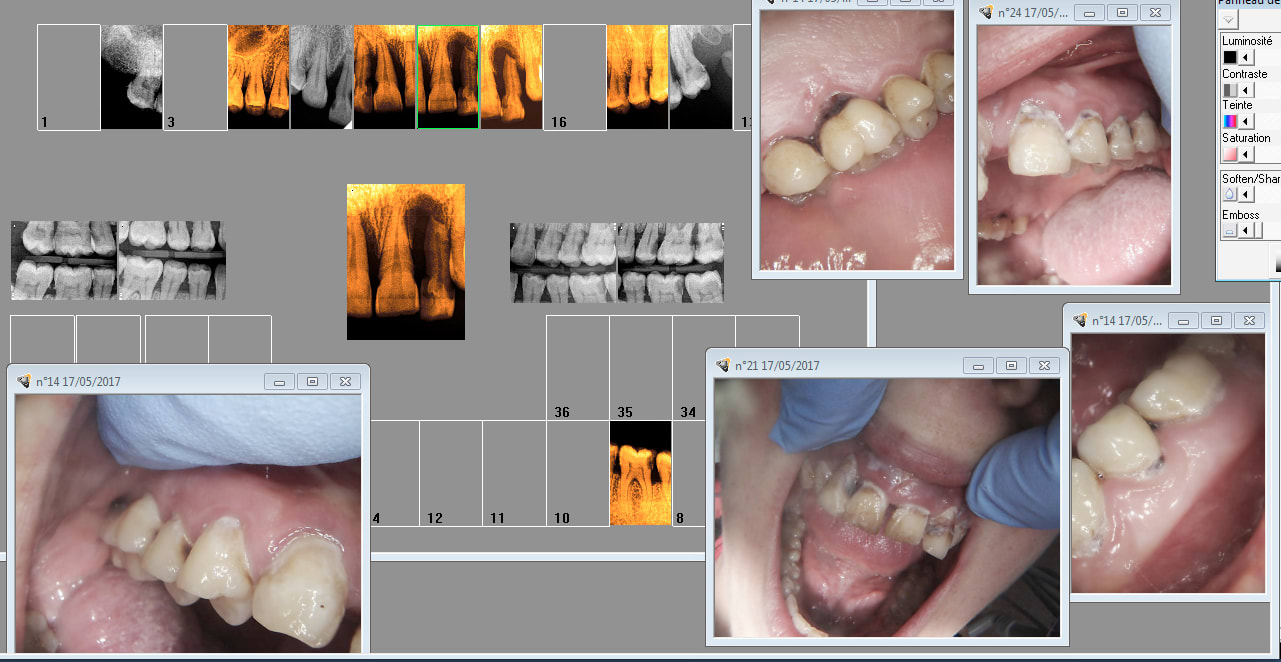

Patiente CMU 34 ans à l'anamnèse ne s'est jamais brossé les dents de sa vie. Consulte pour forte mobilité de la 22.

Bon les 4 incisives sup sont blettes à cause de pb paro sinon des caries de collet et pas trop de dégâts ailleurs.

Pharmacien 75 quand tu as affaire à ce genre de personne qui n'en a strictement rien à branler de ce que tu racontes, tu insistes ?

Capture d écran 2017 05 17 14.58 - Eugenol